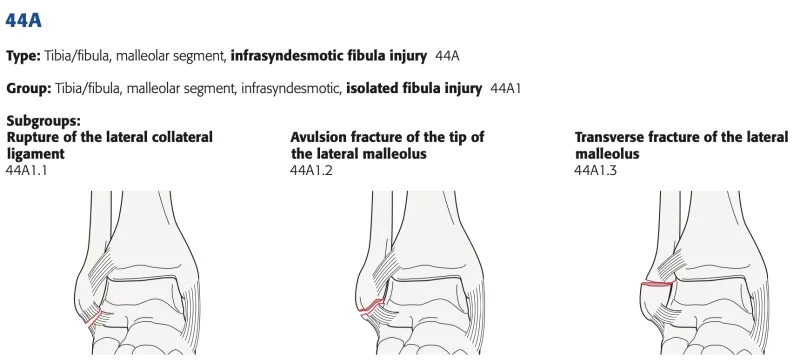

AO/OTA分類は, 44A1.3でした.